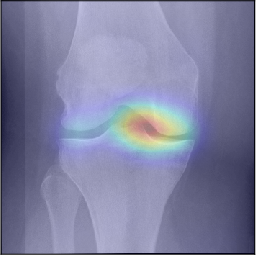

To gain insight into the basis of the CNN’s prediction, we used the GradCAM [24] approach and visualized the attention maps for the well-predicted knees. Examples of attention maps are presented in Figure 5. We observed that in various cases, the CNN paid attention to the compartment opposite to the one where degenerative change became visible during the follow-up visits. Additional examples of such attention maps are presented in Supplementary Figures 3, 4, 5 and 6.

Refer to caption

(a)

(b)

(c)

(d)

Figure 5: Examples of attention maps for progression cases and the corresponding visualization of progression derived using follow-up images from MOST datasets. Here, subplots (a) and (c) show the attention maps derived using a GradCAM approach. Subplots (b) and (d) show the joint-space areas from all the follow-up images (baseline to 84 months). Here, the subplot (b) corresponds to the attention map a) and the subplot (d) corresponds to the attention map (c).